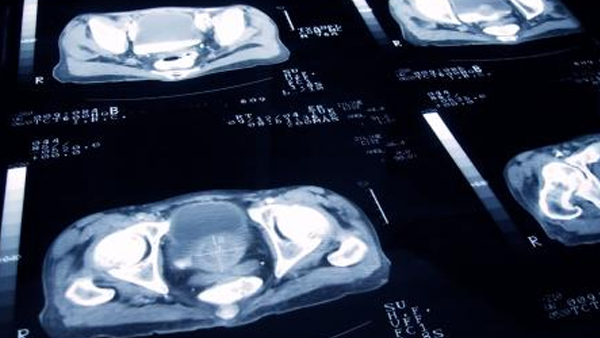

Ракът на простатата е едно от най-често срещаните ракови заболявания при мъжете. Най-често срещаните форми на ракът на простата са аденокарциномите (т.е. раково заболяване, започващо в клетките, които произвеждат и изпускат слуз и други течности). Често ракът на простата в начална фаза няма никакви симптоми. Ракът на простатата в напреднал стадий може да причини по-често уриниране при мъжете или да намали силата на струята, но тези симптоми могат да бъдат причинени също така и от доброкачествени заболявания на простатата.

Обикновено ракът на простатата се развива много бавно. Повечето мъже с рак на простатата са над 65 години и не умират от заболяването. Откриването и лекуването на рака на простатата преди появата на симптомите може да не доведе до подобрение в здравето Ви или продължителността на живота Ви. Говорете с лекаря си за риска от рак на простатата при Вас и дали имате нужда от скринингов тест.